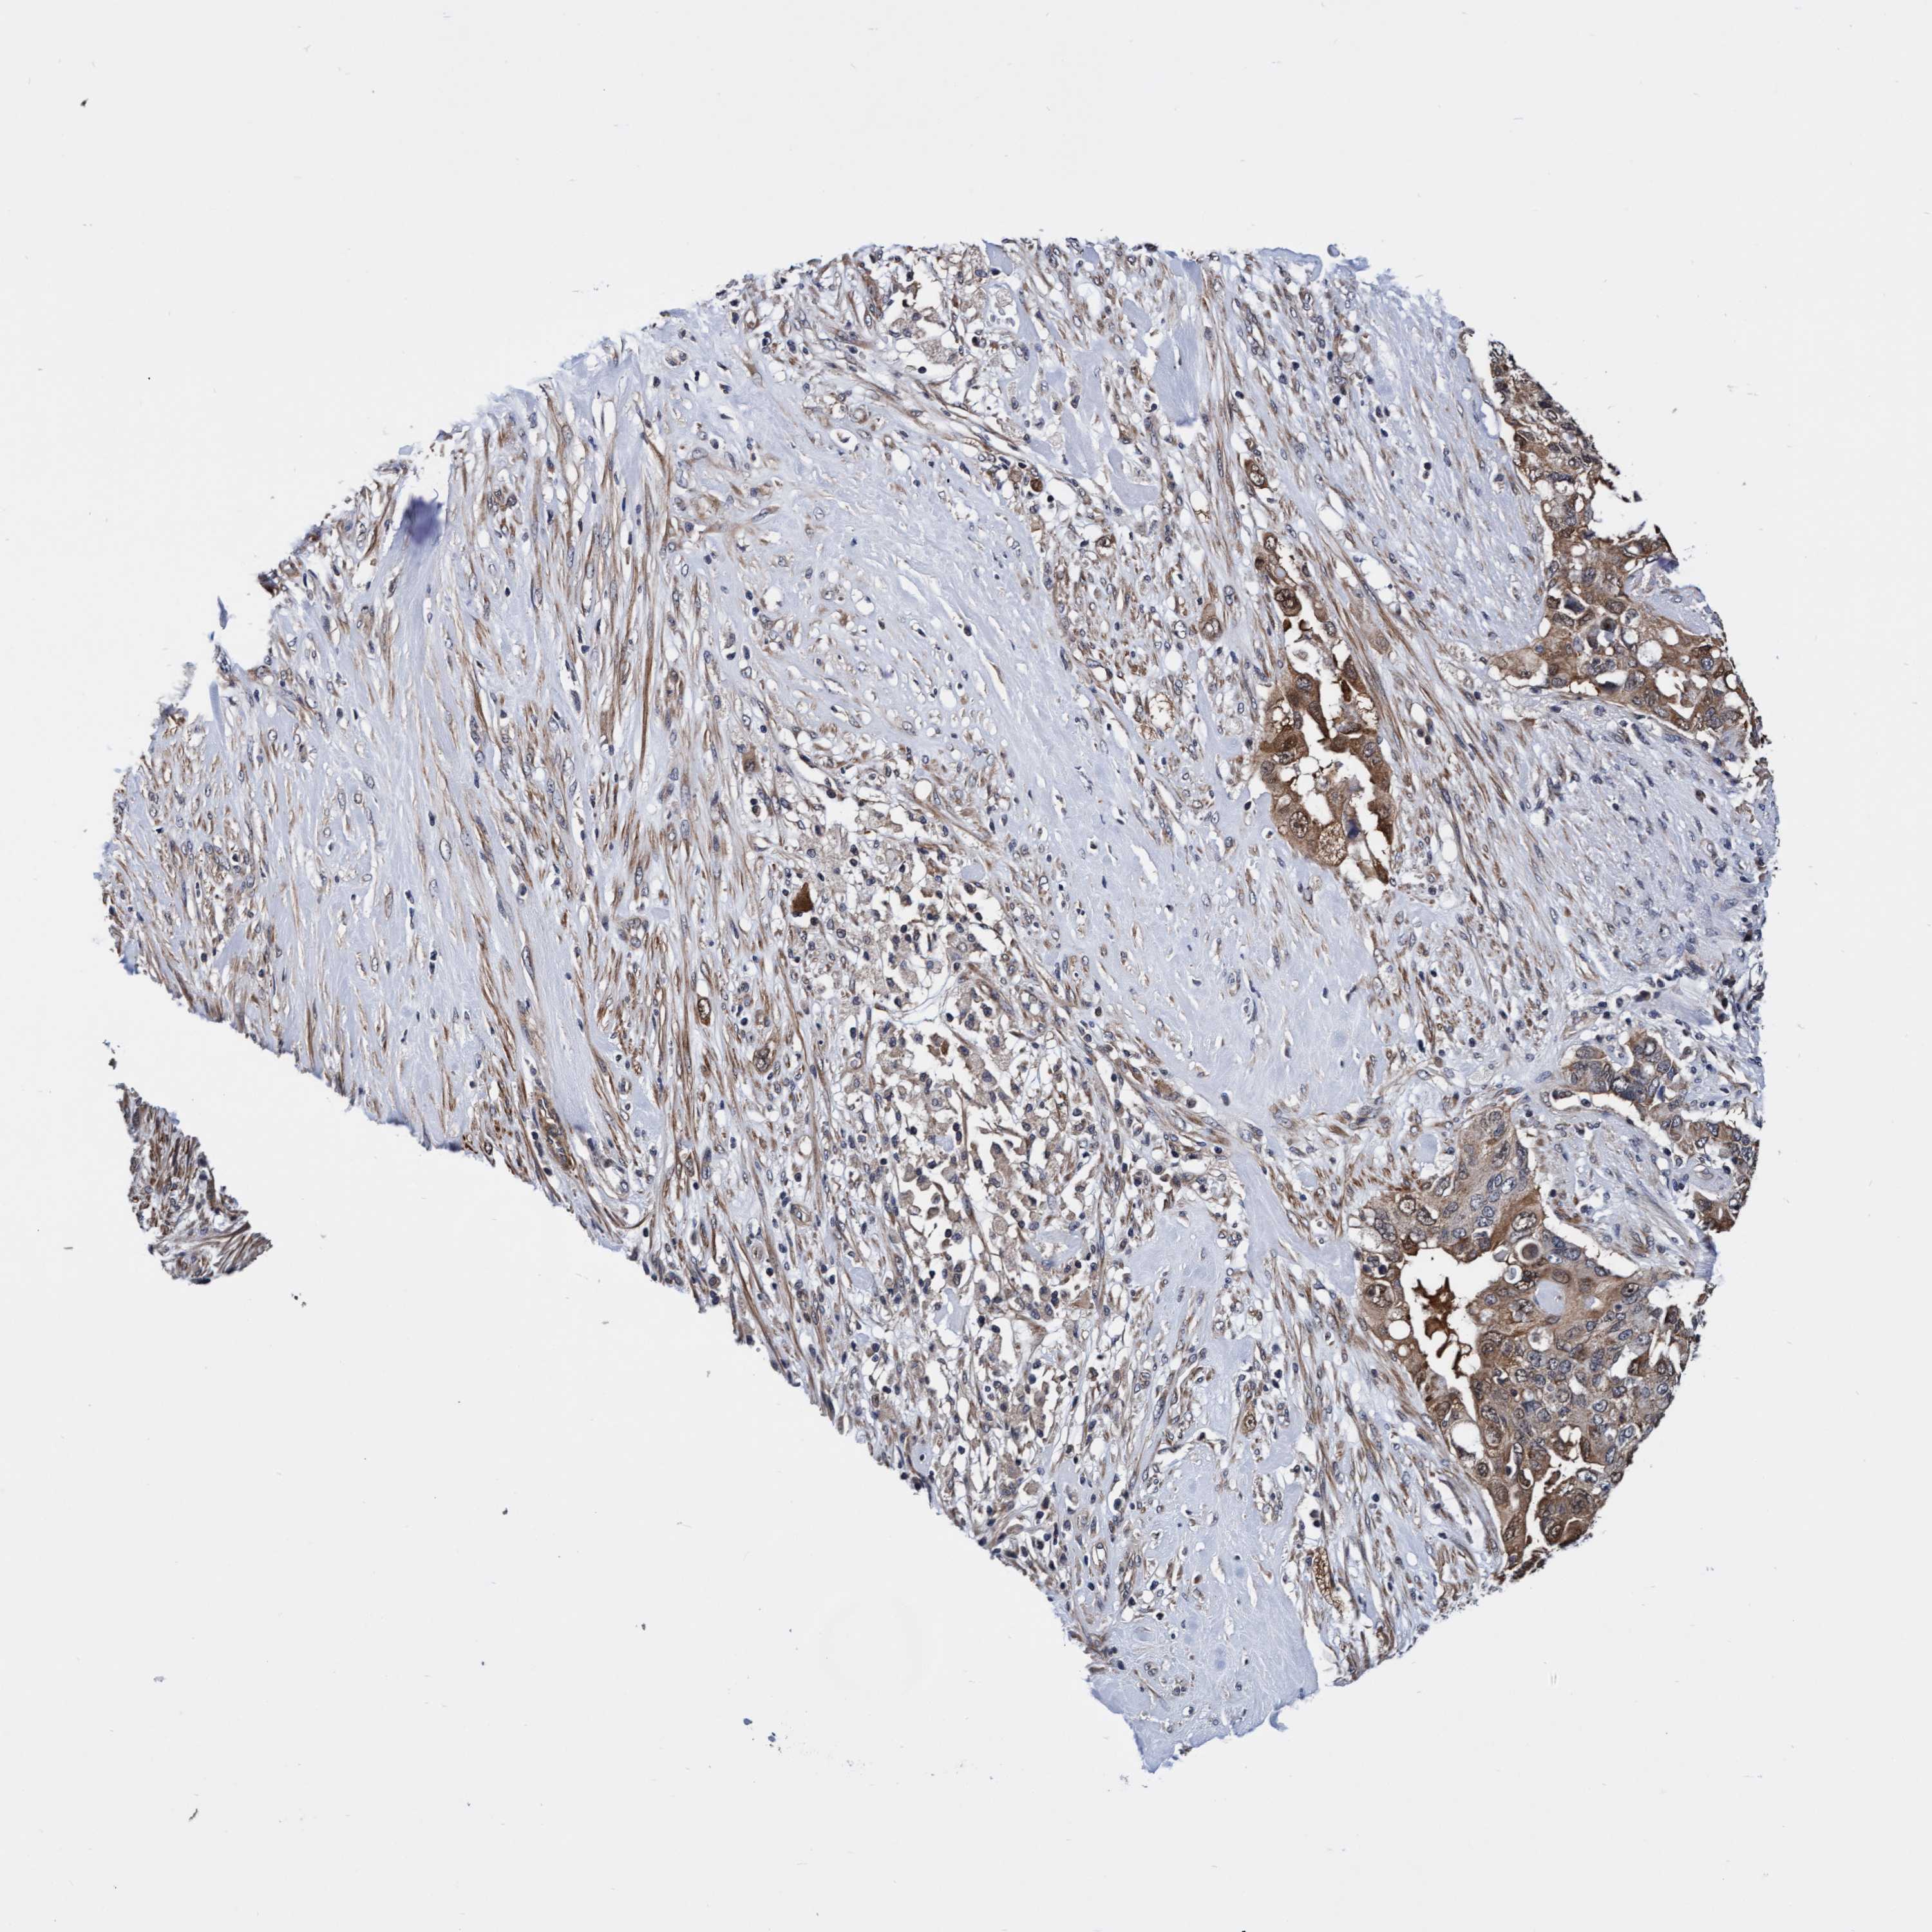

PANCREATIC CANCER - Protein expressioni

A mouse-over function shows sample information and annotation data. Click on an image to view it in a full screen mode. Samples can be filtered based on level of antibody staining by selecting one or several of the following categories: high, medium, low and not detected. The assay and annotation is described here.

Note that samples used for immunohistochemistry by the Human Protein Atlas do not correspond to samples in the TCGA dataset.

Antibody stainingi

Antibody staining in the annotated cell types in the current human tissue is reported as not detected, low, medium, or high, based on conventional immunohistochemistry profiling in selected tissues. This score is based on the combination of the staining intensity and fraction of stained cells.

Each image is clickable and will lead to virtual microscopy that enables deeper exploration of all samples and also displays staining intensity scores, fraction scores and subcellular localization as well as patient and tissue information for each sample.

Antibody HPA021633

Antibody HPA023249

Antibody HPA026561

Antibody CAB002501

Staining

High

Medium

Low

Not detected

Intensity

Strong

Moderate

Weak

Negative

Quantity

>75%

75%-25%

<25%

None

Location

Nuclear

Cytoplasmic/membranous

Cytoplasmic/membranous,nuclear

Adenocarcinoma, NOS

Adenocarcinoma, metastatic, NOS